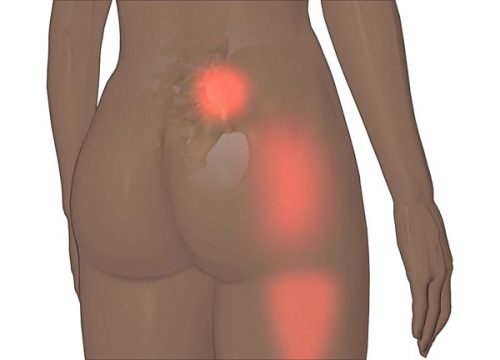

등에는 척추와 골반이 결합되는 특이한 부위가 있다. 이 부분에서 느끼는 불편함은 천장 관절통(Sacroiliac Joint Pain)으로 인한 것이다. 천장 관절에 염증이 생기면 강렬하게 찌르는 듯한 통증이 느껴지는데, 이것은 생각보다 꽤 흔한 질환이다. 이것은 천장 관절염(sacroiliitis) 혹은 천장 관절통(Sacroiliac Joint Pain)으로 알려져 있다.

천장 관절염이나 천장 관절통이 있고 아침에 일어나거나 몇 시간 앉아있다가 일어날 때 더 아플 때, 처음으로 드는 생각이다. 그러므로 천장 관절통에 대해 이야기하기에 앞서 유념해야 할 사항은 천장 관절의 한쪽 혹은 양쪽에 위치한 이런 염증 질환이 진단이 쉽지 않다는 것이다. 이것은 종종 디스크나 일반적인 요통과 같은 다른 문제가 원인이 되기도 한다.

천장 관절통의 증상

천장 관절통은 남성보다 여성에게 더 흔하다. 관절염, 루푸스, 골관절염 혹은 기타 질환 때문에 생기기 때문이다.

- 먼저 엉덩이와 허리에 통증을 느낄 수 있다.

- 그 다음에는 통증이 다리, 사타구니 심지어 발까지 퍼진다.

- 하지만 통증은 계단을 오를 때, 앉을 때, 침대에서 움직일 때 혹은 발걸음을 넓게 걷거나 런지를 할 때 더 심해진다.